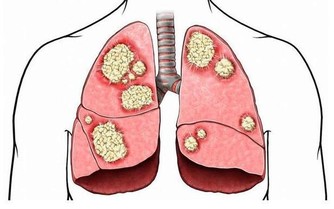

黑棗含有豐富的維生素

有極強的增強體內免疫力的作用,

並對賁門癌、肺癌、吐血有明顯的療效。